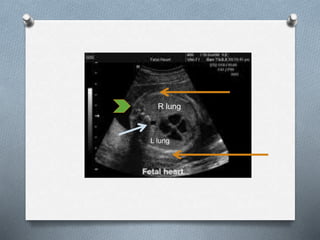

Sonographic Approach:

O four chamber view of

the heart

R lung

L lung

Sonographic Approach: O fourchamber view of the heart

• #15 To be able to determine presence of normal thoracic anatomy, assesment / measurement of the thoracic circumference at the level of the four chamber view of the heart should be obtained. Key view for the assessment of intrathoracic fetal anatomy

• #16 Fundamental plane where heart and lung are assessed On this view, the ff structures can, and should be assessed: Thoracic outline- consisting of 2 displayed ribs and overlying soft tissues and skin. The ribs should be uniformly echogenic, continously smooth, with convex contour and encircle 2/3 of the thoracic area. Two lungs: which occupies 2/3 of the thoracic area. The normal lungs appear symmetric and homogenous with medium level echogenicity increasing gradually as gestation progresses. Echogenicity is slightly increased compared with the liver. Right lung slightly larger than the left. The lungs should abut the thoracic cage with no hypoechoic space in between. Thoracic aorta; lying in the pre vertebral area just left of the midline behind the left atrium One thoracic vertebra: on the midline posteriorly

• #17 This is the axial view of the chest. Its shape is almost circular. The ribs are shown to be uniformly echogenic smooth with convex contour and again encircling 2/3 of the chest wall. The figure B or image B shows where the thoracic circumference should be measured, which is along the outer rib contour excluding the skin and soft tissue.